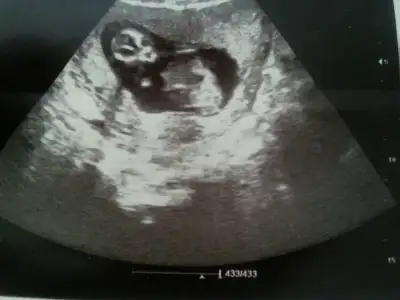

$IMG_0799.webp $IMG_0800.webp $IMG_0801.webp $IMG_0798.webp Merhaba arkadaşlar bende aranıza yeni katıldım.12 Haftalık hamileyim konuyu okuyunca dayanamadım yükledim resimleri.Bakarmısınız sizce ne olabilir bebişimin cinsiyeti

Kızlar fotograflar net deil doktorumuz bu konuda çok iyi değil güzel resim çekemiyor :1: ama gördgüğünüz kadarıyla tahmin söylersniz sevirinim :40::40: tşk :46: